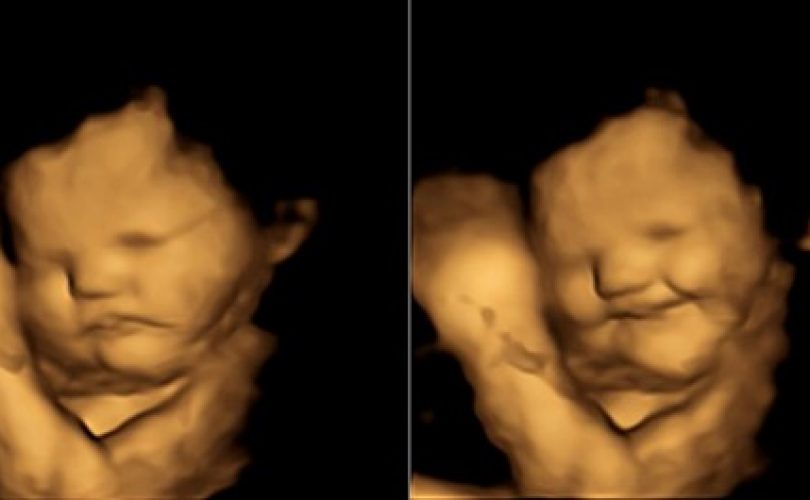

Son bir araştırmaya göre anne karnındaki bebekler dahi tat uyaranlarına tepki gösteriyorlar. Fetüsler annelerinin yediklerini amniyotik sıvıdan algılıyorlar. Araştırmacılar farklı yiyeceklere gösterilen tepkileri ilk kez ultrasonla izlediler. Bebekler daha duymaya ve görmeye başlamadan önce tat duyuları gelişiyor. İlk tat reseptörleri sekizinci hamilelik haftasında gelişiyor ve 15. haftadan itibar...